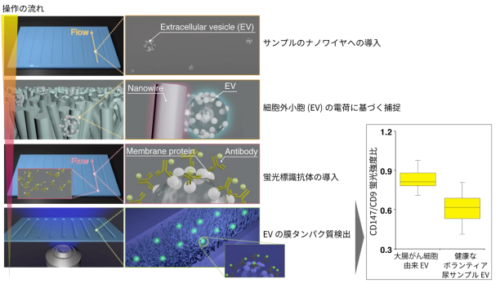

細胞外小胞の新しい捕捉方法を開発~ナノワイヤによって捕捉する細胞外小胞を、がん診断の新しい指標へ~

細胞外小胞(EV)の新しい捕捉方法を開発し、当該方法で捕捉するEVのmiRNA(マイクロRNA)や膜たんぱく質の発現量が...